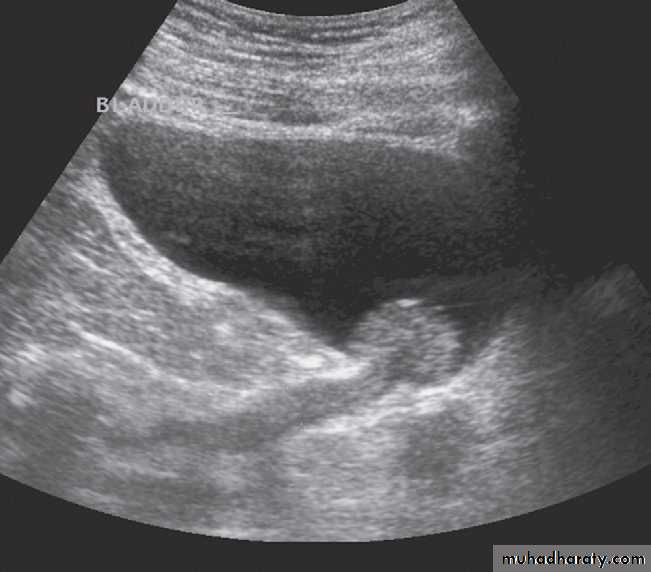

Ultrasound Dilatation of the pelvicaliceal system ( hydronephrosis ) is demonstrated sonographically as a multiloculate fluid collection in the central echo complex, caused by pooling of urine within the distended pelvis and calices .

Major DDX are multiple renal cysts. With prolonged obstruction, thinning of the cortex due to atrophy will be seen.

Some causes of obstruction are identifiable (e.g. carcinoma of the bladder or a stone at the vesicoureteric junction), it is often not possible to determine the cause of urinary tract obstruction at ultrasound examination.